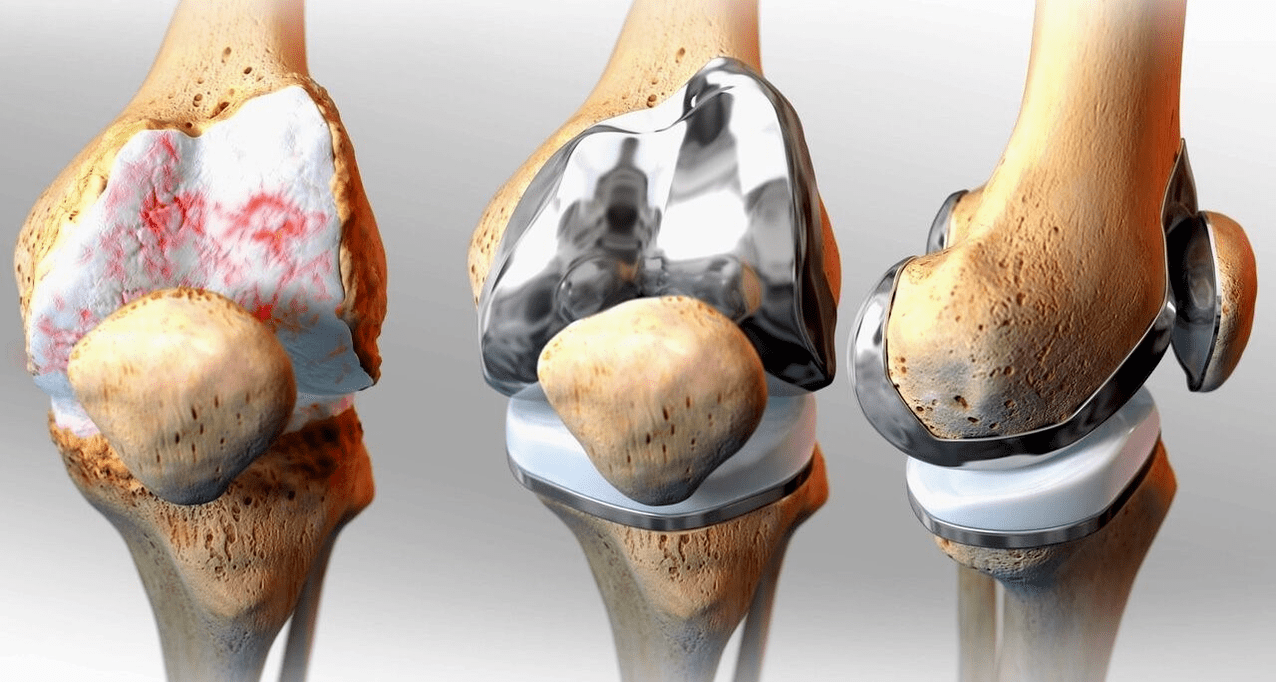

Surgical treatment and endoprosthetics

Endoprosthesis replacement is a common and effective surgical method for treating severe gonarthrosis, which allows you to maintain limb mobility and the ability to lead a full life subsequently.This is a high-tech operation lasting approximately one and a half hours.In the postoperative period, long-term rehabilitation and development of the joint are necessary.After 25-30 years, when the artificial joint wears out, it needs to be replaced again.